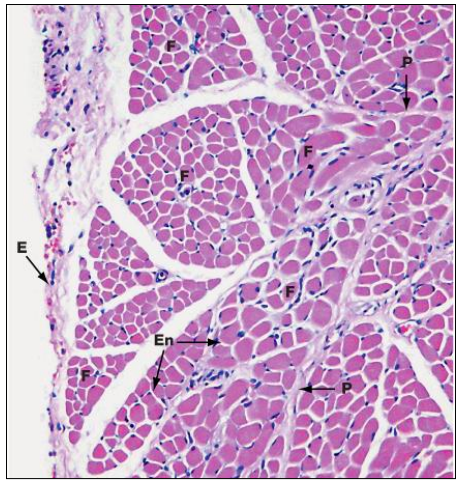

Name the layers of Skeletal Muscle

Epimysium – dense CT

What is this a cross-section of

Skeletal muscle